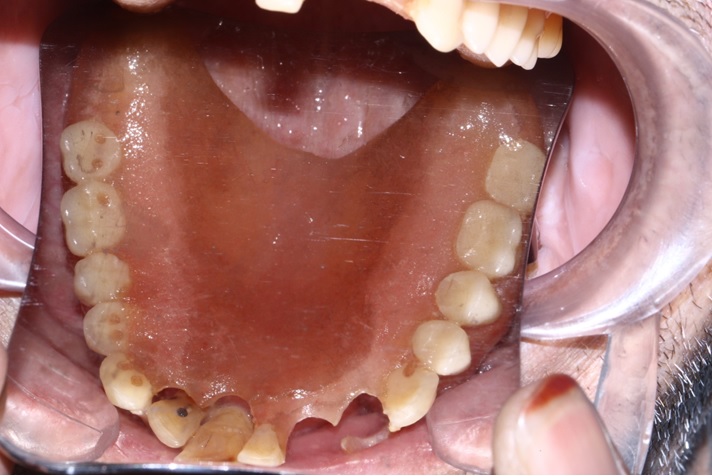

Tall and Tilted Pin Hole Immediate Loading ( TTPHIL) is a modern and most reliable technique for dental implantation. The special feature of such method is that dentist combine long and wide implants with bi-cortical support bone.

The All on 6 and All on 4 technique apply that method of implants placement.

This case report show the successful All on 6 dental implantation using Alpha Dent implants.